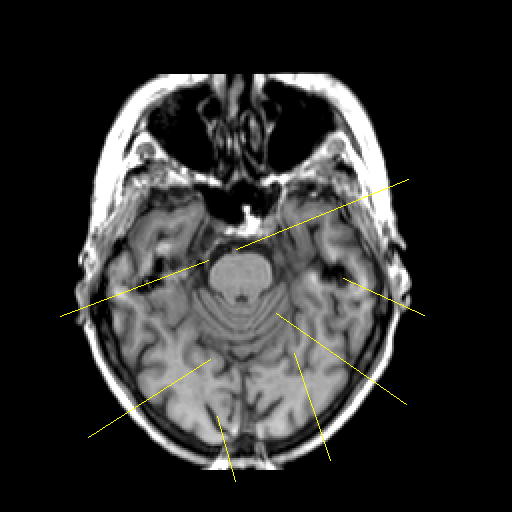

T1-weighted structural MR: Slice 17

Slice 17

Pointers

Labeled